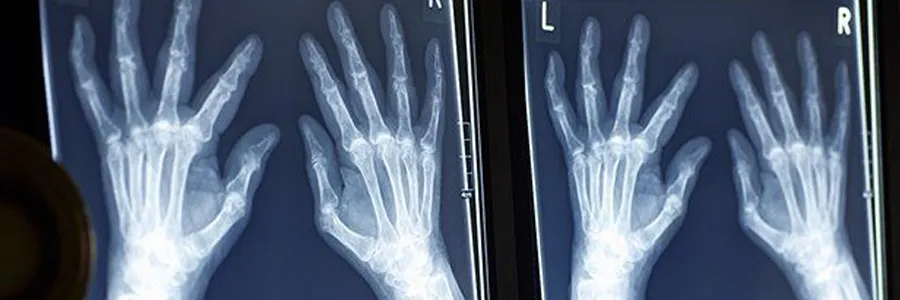

Karıncalanma

Elleriniz, ayaklarınız veya bacaklarınız “iğneler ve iğneler” içindeymiş gibi mi hissediyorsun? B12 eksikliği sinirlerinizi kaplayan koruyucu kılıfa zarar verebilir. B12 eksikliği depresyona, kafa karışıklığına, hafıza sorunlarına neden olabilir. Ayrıca dengenizi de etkileyebilir.